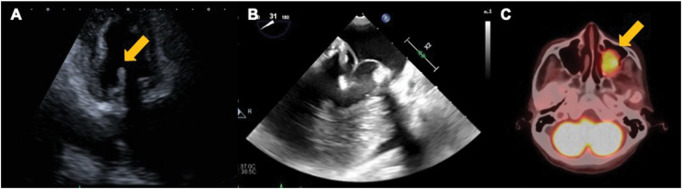

We report a case of recurrent nonbacterial thrombotic endocarditis (NBTE) following vegetectomy of bioprosthesis without malignancy or autoimmune disorders. A 76-year-old woman underwent mitral valve replacement with a bioprosthesis for mitral regurgitation. Six years later, an outpatient echocardiography revealed a mobile vegetation incidentally. No signs of infection were observed, and various tests ruled out malignancy or autoimmune disorders. Pathological findings after an urgent vegetectomy also showed no signs of infection, and the diagnosis was NBTE. Anticoagulation therapy with warfarin was continued, but 1 year after surgery, an outpatient echocardiography revealed NBTE recurrence. After the patient underwent anticoagulation therapy with heparin and resection of the papilloma of the maxillary sinus, the vegetation disappeared, and there has been no recurrence. Since NBTE can recur, strict lifelong follow-up with anticoagulation therapy might be required.